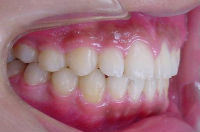

治療開始時 治療終了時

前歯の歯並びが乱れている子供の症例。<出っ歯> 医療法人社団 クオリタス いずみ歯科矯正歯科医院 (浦安市)

前歯の歯並びが気になり来院される患者さんが多いです。

出っ歯の位置を改善する事により

今回の症例は独自の方法とt4kなどによって改善しました。